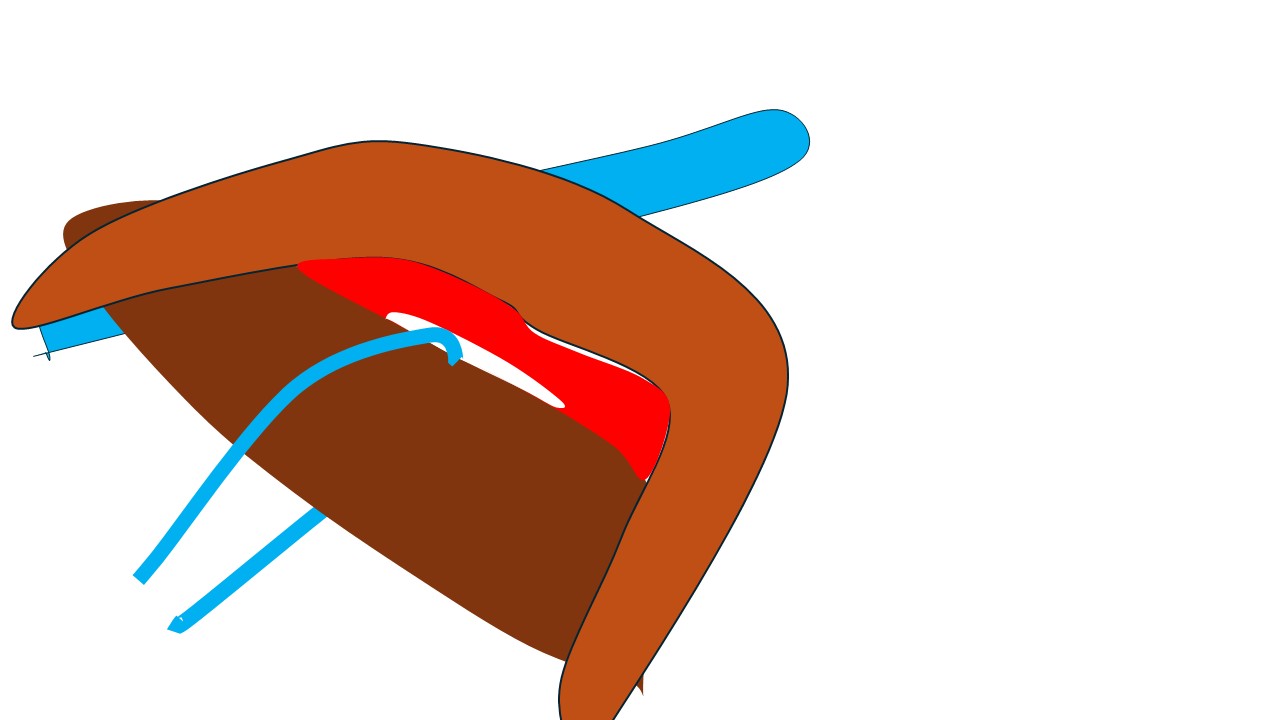

それではどうしたのか?

小胸筋を切断します。(左図)

そして、鎖骨下静脈に被さって視野の妨げとなっている部分を持ち上げます。(右図)

すると…

このように(左図)鎖骨下静脈と鎖骨下リンパ節の関係を(何にも邪魔されずに)直視できる+(鎖骨下リンパ節が持ち上がることによって)「鎖骨下静脈と鎖骨下リンパ節の「接合面」を直視できるのです。(右図)

(矢印のように)慎重に左右から少しずつ外していき、遂に「郭清完了!」となったのです。

小胸筋膜の「こちら側」だけの視野しか持っていなければ(鎖骨下郭清できない乳腺外科医達)とても、その「向こうにあるリンパ節」に手はとどきません。

ましてや、その向こう側で血管に被さって視野を塞いでいるような「鎖骨下リンパ節」の摘出は「夢のまた夢」となるでしょう。

視野の確保が如何に重要か?